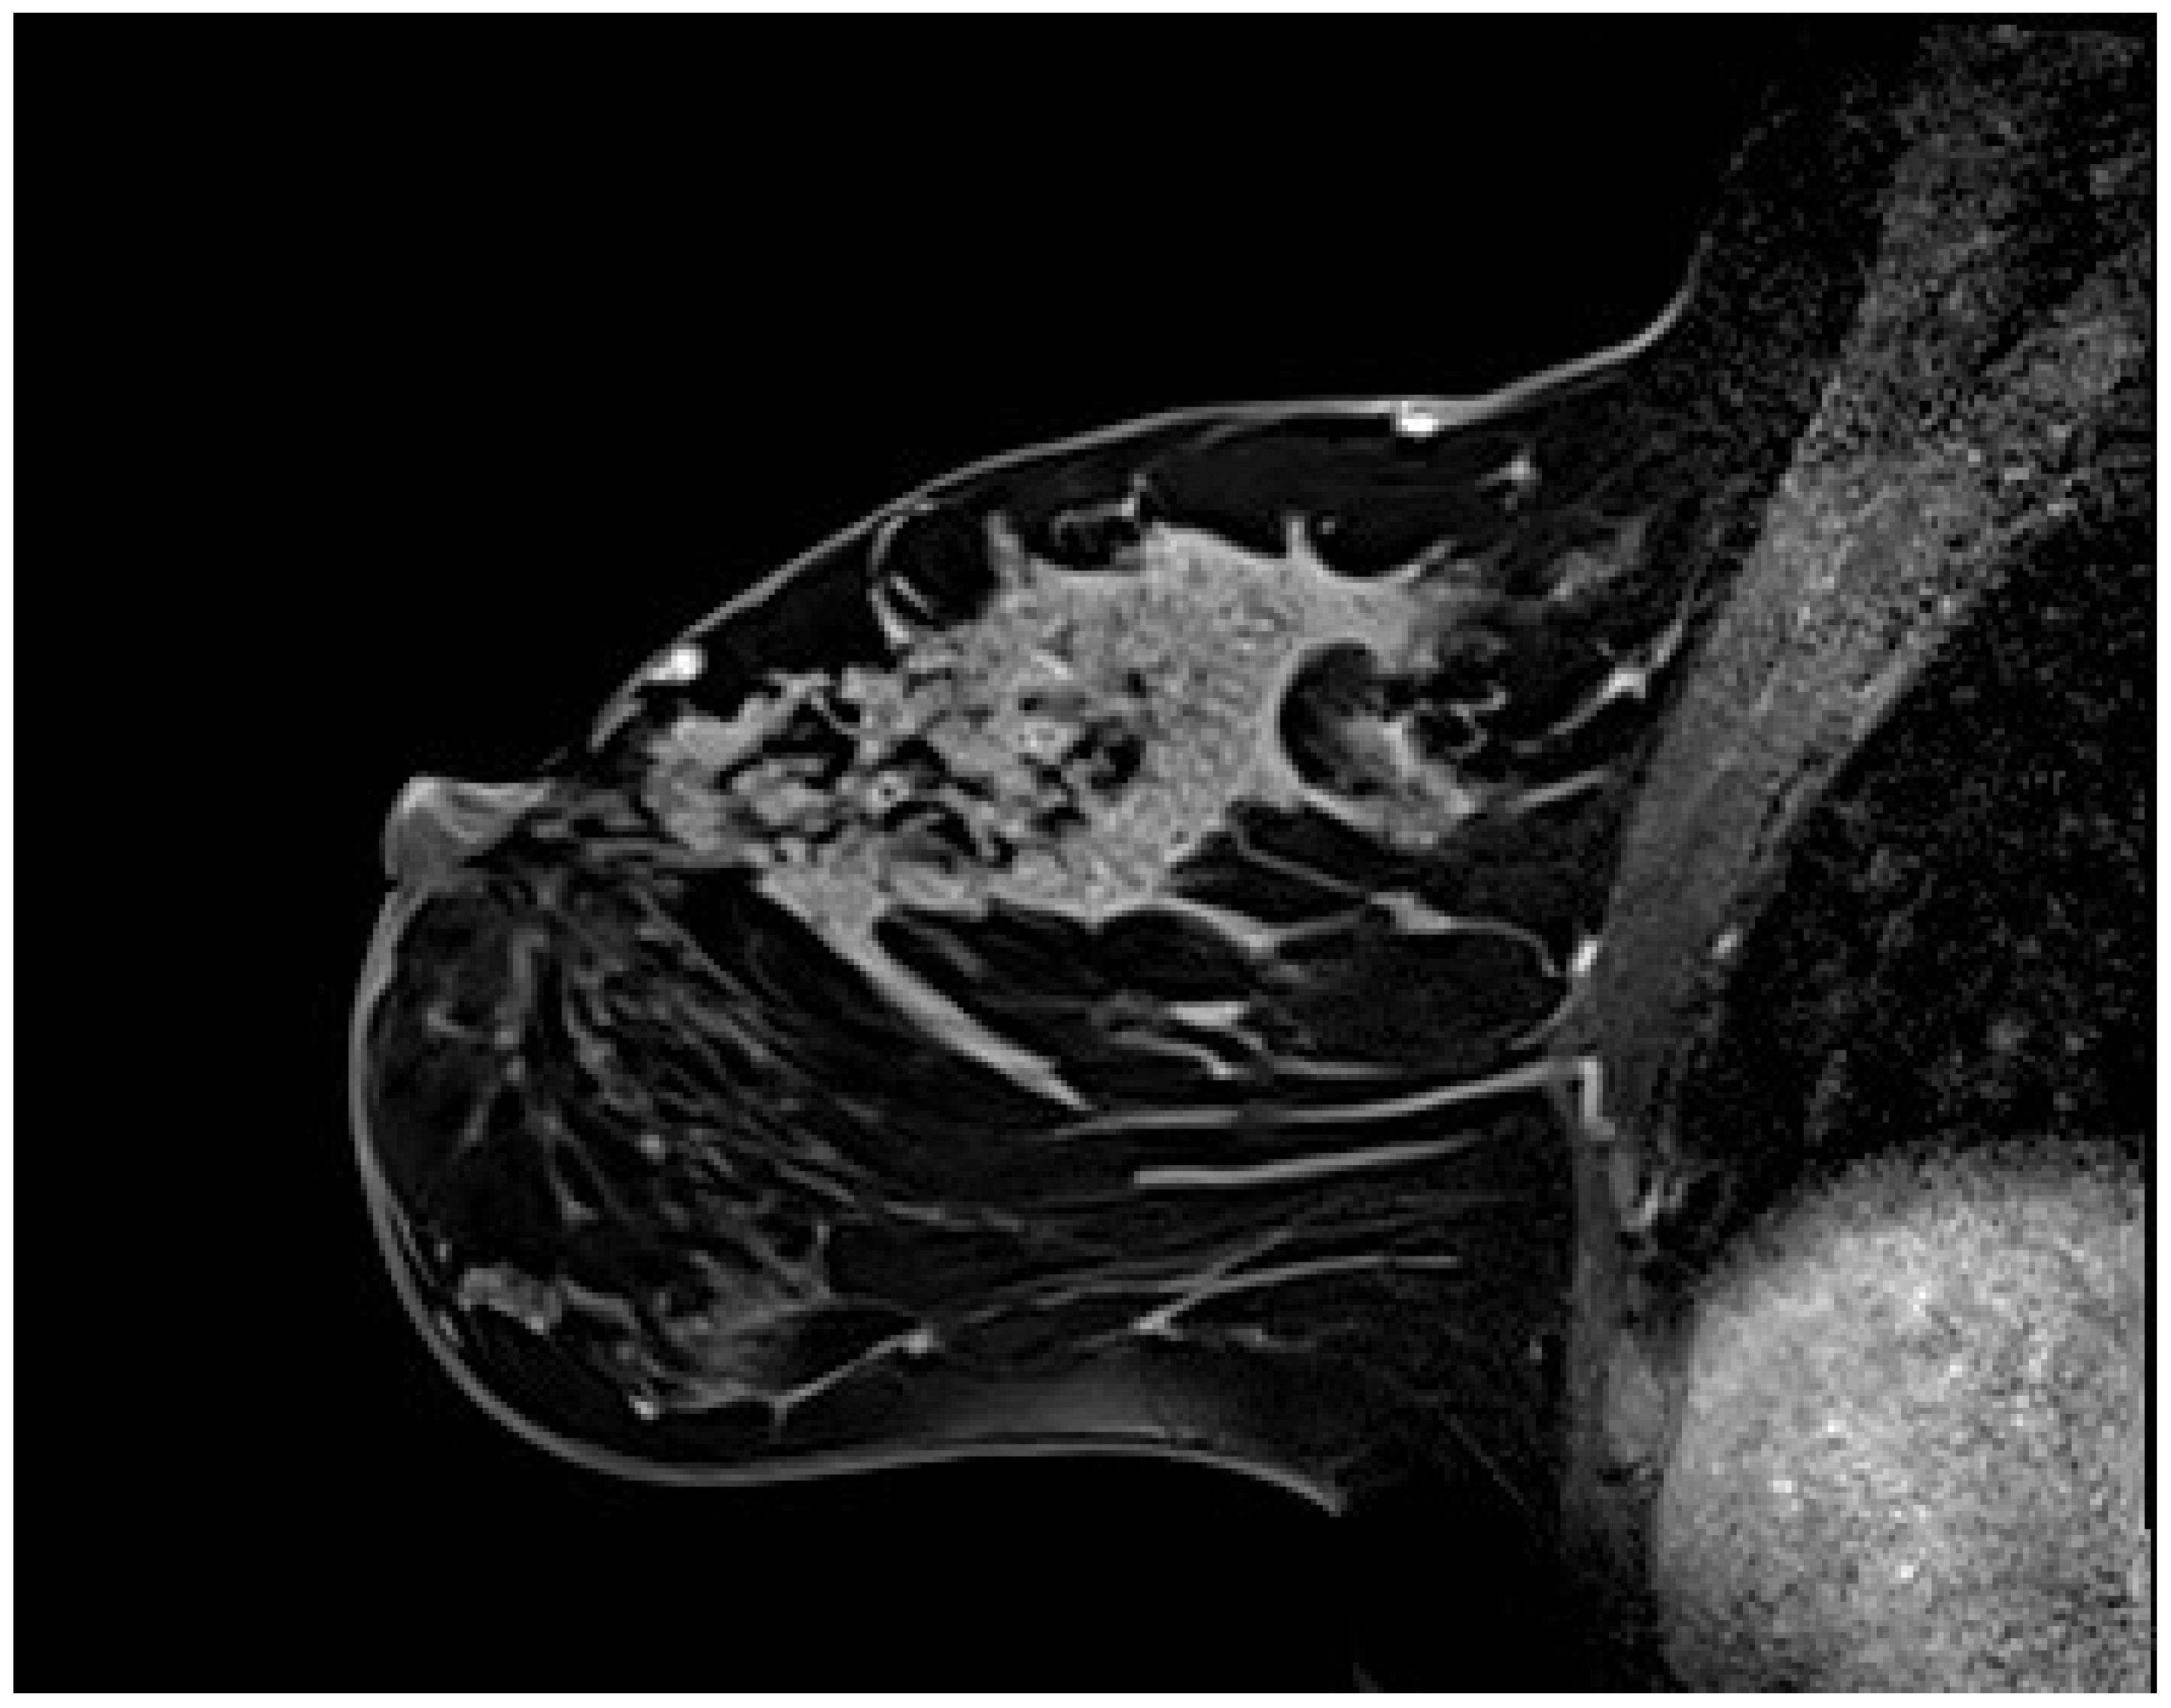

Figure 3. Breast magnetic resonance imaging findings in a 37-year-old woman with segmental nonmass enhancement (NME) exhibiting a mixed internal enhancement pattern. (a) Short tau inversion recovery sequence reveals cystic components within the lesion. (b) Post-contrast image demonstrates segmental NME with clustered ring and heterogeneous internal enhancement. (c) Dynamic contrast-enhanced imaging shows rapid initial contrast uptake followed by a washout pattern in the delayed phase. Histopathological analysis confirmed ductal carcinoma in situ.